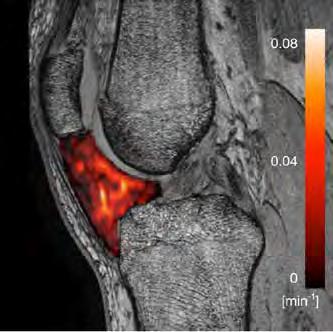

The activities of the MR Physics group are driven by clinical research lines of the Radiology and Nuclear Medicine department such as musculoskeletal research (with Edwin Oei), Lung MRI (with Harm Tiddens and Pier Luigi Ciet) and neuro-oncology (with Marion Smits). Besides the clinical research lines, it is important to notice that several fruitful projects are carried out on technical developments.